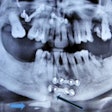

X-Ray: Page 7